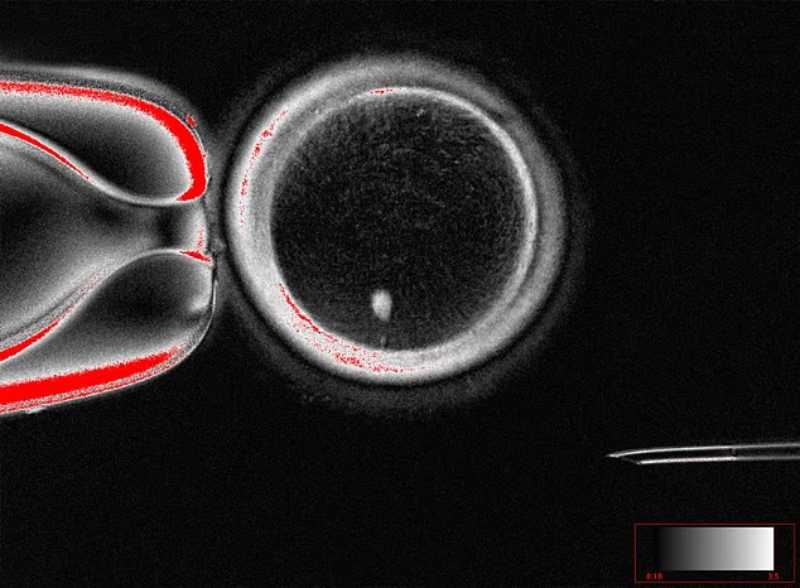

A mitomeiose surge justamente para contornar esse problema. A técnica consiste em forçar um núcleo somático em estado G0/G1 (2n2c), ou seja, sem duplicação prévia do DNA, a entrar prematuramente em metáfase dentro do citoplasma de um oócito humano enucleado. Assim, o genoma somático é induzido a passar por uma divisão “redutiva” semelhante à meiose, ainda que sem todos os mecanismos naturais de recombinação.

Os pesquisadores observaram que os oócitos reconstruídos com núcleos somáticos conseguiam formar fusos bipolares, mas não respondiam adequadamente à ativação induzida por espermatozoides.

Para superar essa limitação, foi necessário recorrer a uma ativação artificial por meio da combinação de eletroporação com roscovitina, um inibidor seletivo de quinases dependentes de ciclina. Esse protocolo permitiu a extrusão de corpúsculos polares e a formação de pró-núcleos, sinalizando que a segregação cromossômica havia ocorrido.

A análise detalhada do conteúdo cromossômico revelou que, em média, 23 cromossomos somáticos eram retidos no zigoto, número equivalente ao esperado para um gameta humano. No entanto, diferentemente da meiose natural, a segregação foi aleatória e não houve recombinação entre cromossomos homólogos. Mesmo assim, os embriões derivados desses zigotos foram capazes de iniciar divisões mitóticas e, em alguns casos, atingir o estágio de blastocisto.